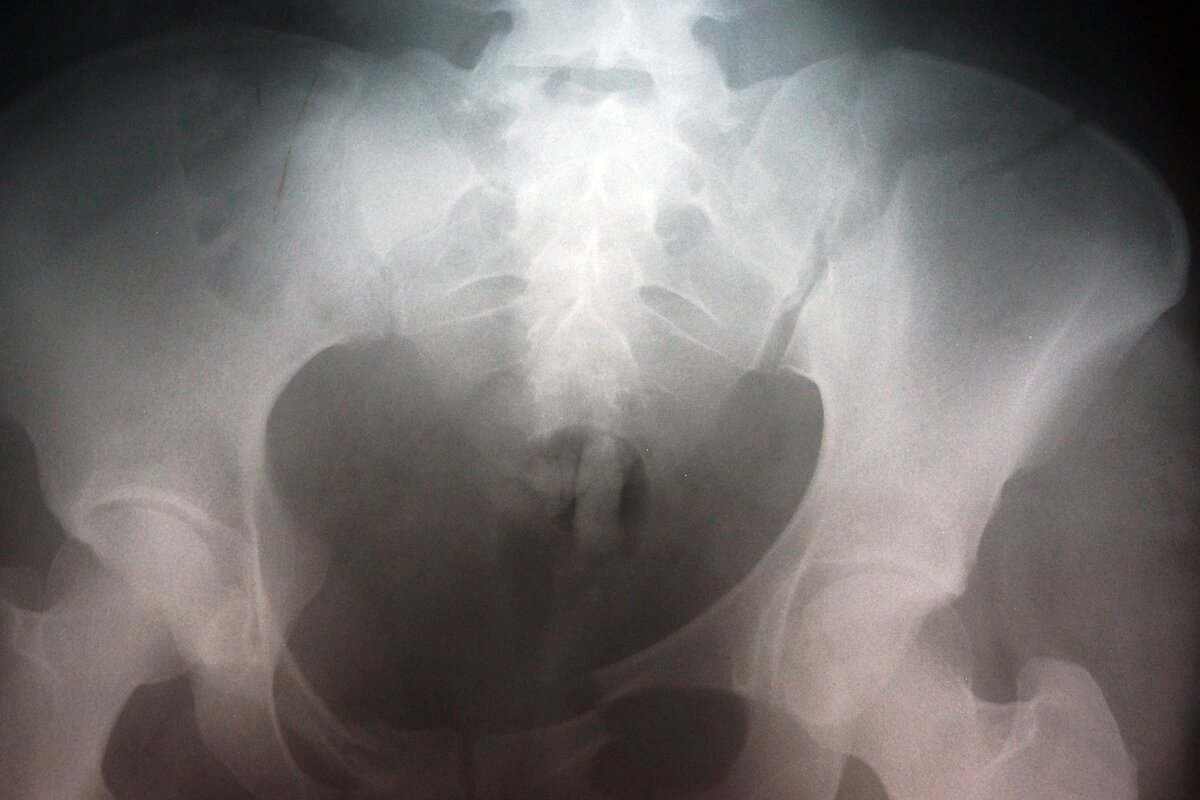

Фото: m24.ru